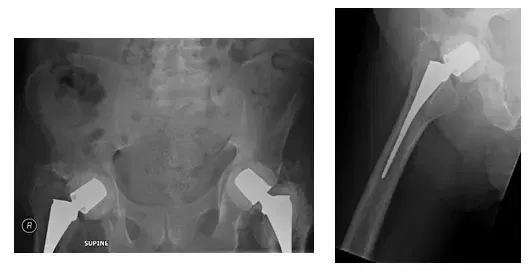

Láminas de control intraoperatorio. Las imágenes muestran la colocación del espaciador de cemento de ambas cabezas y cuellos femorales presumiblemente. Las radiografías muestran dosis altas de antibióticos espaciadores

La radiografía muestra la pelvis tras la colocación de cemento bilateral en la cadera. Las radiografías muestran espaciadores de cemento

Las radiografías muestran un espaciador bilateral de cadera sin aflojamiento ni fracturas pélvicas

El paciente había seguido un seguimiento cada pocos meses para controlar su evolución. Posteriormente se ha presentado sin dolor, con una buena amplitud de movimiento y soporta peso según lo tolera.